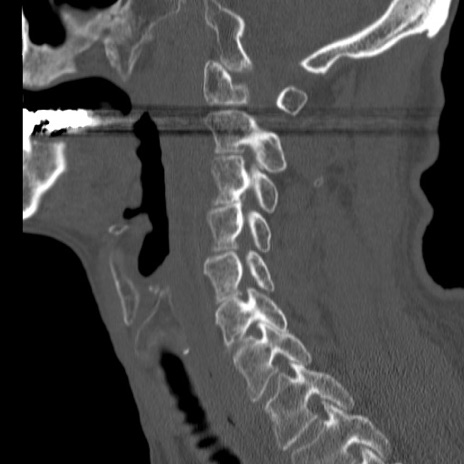

症例46 頚椎CT(矢状断像)

【症例】80歳代男性

【主訴】両側頚部〜上肢のしびれ

【現病歴】昨日、自宅内で転倒、その後より上記症状あり。意識障害なし。

【身体所見】両側上肢のallodynia(熱痛覚過敏)あり。MMTおよびDTRは正確な所見取れず。両上肢の挙上はなんとか可能。

異常所見と診断は?